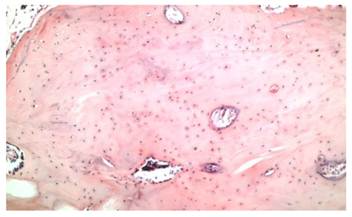

Figure 7

Compact tissue within a loose connective tissue containing apposition and resorption lines(X100, H&E).

Dental volumetric tomographic (DVT) images showed multiple osteomas of the buccal cortex of the right mandibular angle and left mandibular angle (Figure 3,4). Additionally, in the coronal and sagittal sections of the mandible condyle, a huge osteoma that limited mouth opening was diagnosed (Figure 5). Cephalometrically, he showed a slightly retrusive maxilla with an ANB angle of 1˚and a relatively normal mandibula in anterioposterior direction. His mandibular plane angle (S-N / Go-Me: 25˚) and articular angle (S-Ar-Go: 133˚) were reduced (Table 1). His profile was straight due to the slightly retruded maxilla position. According to the Steiner's S line his lips were in normal position (Figure 6). The osteomas were submitted for pathologic examination. Histopathologic examination revealed that the specimens displayed a normal-appearing dense compact lamellar bone with minimal marrow spaces and rare irregular Haversian canals that did not show osteoclasts or osteoblasts (H&E X100)(Figure 7). Due to the dental anomalies, the osteomas in the mandible and the familial history of the patient, the patient was diagnosed as GS. Following resection of the osteomas that caused discomfort, prosthetic rehabilitation was performed.